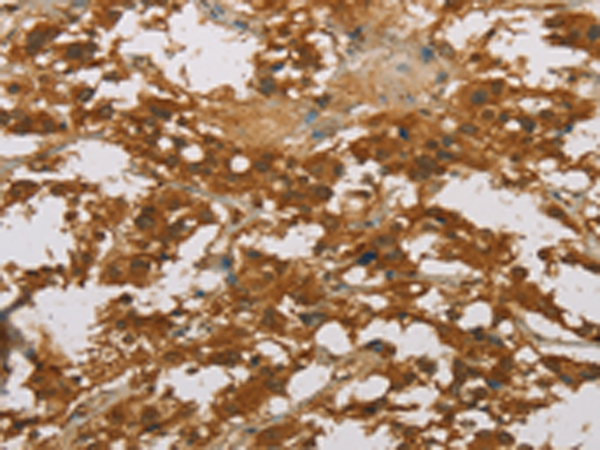

分类: 科研抗体货号: P08182别名: p38; CRKII应用: IHC反应种属: Human, Mouse, Rat